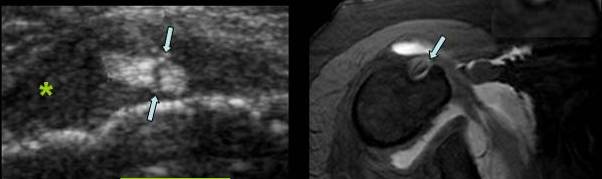

CHIST MUCOID INTRANEURAL AL NERVULUI ULNAR

Parestezii de lunga durata a degetelor 4 si 5

Structura chistica ce disociaza filetele nervoase → cu hiperemie in perinerv →

Pe IRM se evidentiaza hipertrofie nervoasa in T2 si prinde contrast in periferia chistului in T1